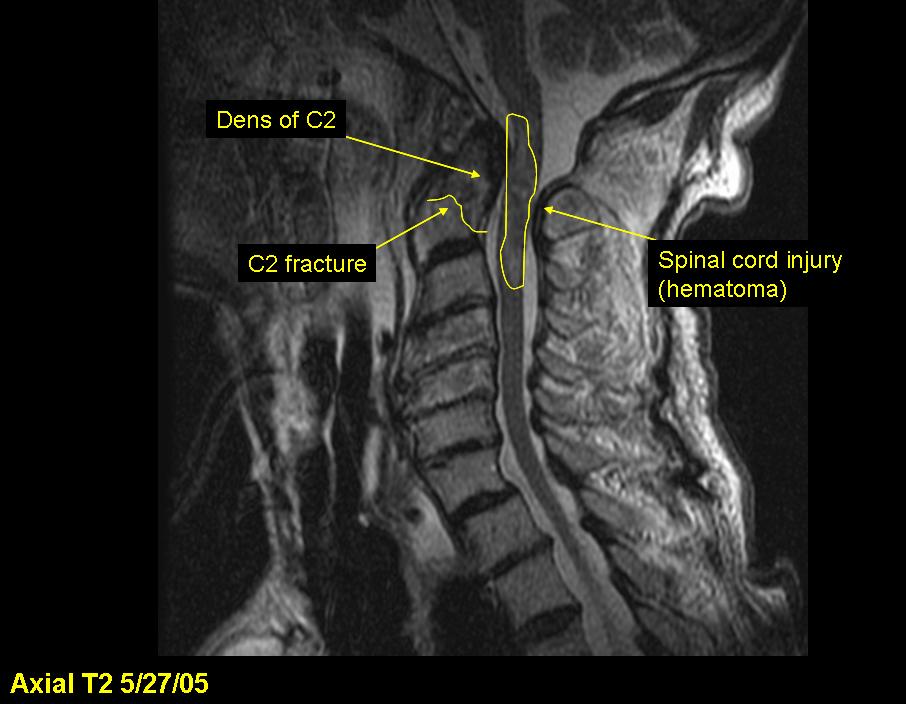

X-ray, CT, and MRI image studies at the hospital show C1 and C2 fractures with spinal cord injury, resulting in quadriplegia. T2-T4 spinous processes and several left ribs are also fractured. The patient never regains consciousness and dies the next day.

The dens, also called the odontoid process, is the portion of the C2 (the "axis") about which the C1 and the head rotate. Because the dens extends superiorly into the ring of C1, it is subjected to shear forces and fracture from C1 in neck injuries. The dens can then impact the spinal cord, injuring or severing it. In this case, although the patient's spinal cord was not severed, impact from the dens caused a spinal cord hematoma resulting in quadriplegia.